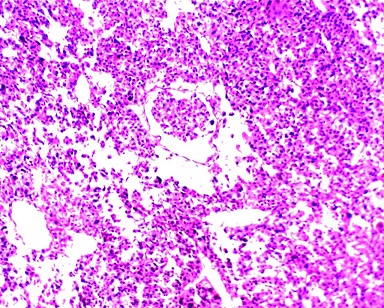

Histological Images Of The Tumor In The Pancreatic Tail And

Non Functioning Adrenocortical Carcinoma Report Of A